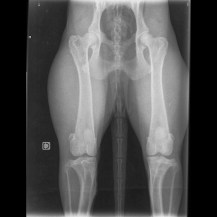

A noter que concernant la dysplasie de la hanche, il existe 5 stades (degrés) :

stade A : in demne de dysplasie ; stade B : état sensiblement normal ; stade C : dysplasie légère ; stade D : dysplasie moyenne ; stade E : dysplasie grave.

Tous nos reproducteurs ont leurs radios de dépistages des dysplasies hanches et coudes faites. Les résultats son visibles sur leur fiches sur le site de la société centrale canine ainsi que dans les albums photos .